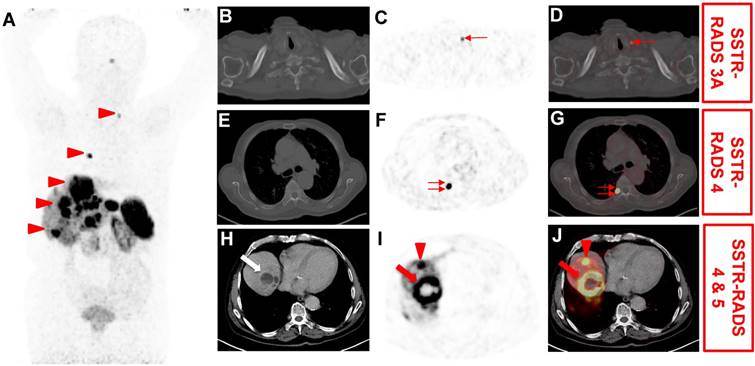

SSTR-RADS-1A refers to benign lesions, without any abnormal uptake (L 1) and SSTR-RADS-1B (L 2-3) to benign lesions, but with focal uptake (e.g. benign prostatic hyperplasia). SSTR-RADS-2 (L 1) includes uptake in soft-tissue sites or bone lesions atypical of metastatic NET rendering such lesions likely benign, e.g. uptake in a bone lesions suggestive to be degenerative (e.g. a Schmorl node). SSTR-RADS-3 is segregated into 4 sub-classifications and is focused on the concept of equivocal findings on SSTR-targeted PET, which may need further work-up. SSTR-RADS-3A and SSTR-RADS-3B lesions (L 1-2, respectively) are suggestive of, but not definitive for NET. While SSTR-RADS-3A describes lesions that demonstrate equivocal uptake in soft-tissue sites typical for NET (e.g. a regional lymph node), SSTR-RADS-3B includes such lesions in the skeleton (e.g. low-level uptake in the rib). On the other hand, SSTR-RADS-3C lesions are suggestive of an SSTR-expressing, non-NET benign tumor or malignant process, i.e. uptake (up to L 3) at a site highly atypical for NET, such as the breast. SSTR-RADS-3D sites are not SSTR-avid and have a high likelihood for a dedifferentiated NET lesion or another type of non-SSTR-expressing malignancy, i.e. further work-up to rule out potential tumor escape or secondary malignancy is mandatory. SSTR-RADS-4 and -5 have both a high level of uptake (L3) at typical disease sites. SSTR-RADS-4 does not show corresponding findings on conventional imaging, while SSTR-RADS-5 does demonstrate such findings. Notably, in terms of multiple lesions, an overall scan impression can be indicated by establishing an overall SSTR-RADS score (highest target lesion score takes priority over the other lesion, Figure 4).

Figure 4

Application of somatostatin receptor reporting and data system (SSTR-RADS) for the interpretation of SSTR-targeted PET/CT [8]. 76 year-old male with history of a cancer of unknown primary (most likely primary hepatic NET), which underwent [68Ga]-DOTATOC PET/CT for staging. (A) Whole body maximum intensity projection demonstrated multiple suspicious uptake sites (arrowheads). On (B) axial CT, (CT) axial PET and (D) axial PET/CT, mild radiotracer uptake is seen in a left supraclavicular lymph node (thin arrow). This lesion was classified as SSTR-RADS 3A by an experienced reader. On (F) axial PET and (G) axial PET/CT, intense radiotracer uptake is visualized in the head of the 7th right rib (double thin arrows). As this site of radiotracer uptake did not show corresponding findings on (E) axial CT, this finding was classified as SSTR-RADS-4. On (H) axial CT, (I) axial PET and (J) axial PET/CT, intense radiotracer uptake is visualized in a liver lesion (segment VII/VIII, arrow), which shows central necrosis and subtle hypodensity on (H) axial CT. Thus, this lesion was classified as SSTR-RADS Score 5. Another liver lesion in segment VIII/IVa (arrowhead) also demonstrated intense radiotracer uptake on (I) axial PET and (J) axial PET/CT, but without corresponding findings on (H) axial CT, i.e. SSTR-RADS-4. The Overall SSTR-RADS Score was 5. Based on this scoring, peptide receptor radionuclide therapy may be considered [8].